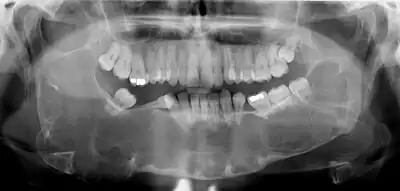

Diagnosis is usually radiological. However, definitive diagnosis is through biopsy. Aspirational biopsy of odontogenic keratocysts contains a greasy fluid which is pale in colour and contains keratotic squames.[12][2] Protein content of cyst fluid below 4g% is diagnostic of odontogenic keratocysts.[2] Smaller and unilocular lesions resembling other types of cysts may require a biopsy to confirm the diagnosis.[9] On a CT scan, the radiodensity of a keratocystic odontogenic tumour is about 30 Hounsfield units, which is about the same as ameloblastomas. However, ameloblastomas show more bone expansion and seldom show high density areas.[13]

Radiographs of odontogenic keratocysts show well-defined radiolucent areas with rounded or scalloped margins which are well demarcated.[12] These areas can be multilocular or unilocular. The growth pattern of the lesion is very characteristic from which a diagnosis can be made as there is growth and spread both forward and backward along the medullary cavity with little expansion. No resorption of teeth or inferior dental canal and minimal displacement of teeth is seen. Due to lack of expansion of the odontogenic keratocyst, the lesion can be very large when radiographically discovered.[9]

Early odontogenic keratocysts usually do not display symptoms. Typically, clinical signs and symptoms present with bony expansion, or infection. However, bony expansion is uncommon as odontogenic keratocysts grow due to increased epithelial turnover rather than osmotic pressure. When symptoms are present they usually take the form of pain, swelling and discharge due to secondary infection. Odontogenic keratocysts are usually noted as incidental radiographic findings. Radiographically they can be seen as unilocular or multilocular radiolucencies. They can be mistaken for other cysts such as residual cysts or a dentigerous cyst if they occur over an unerupted tooth.[7]